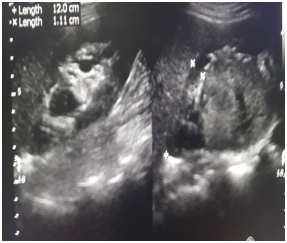

In males, the prostate surrounds a part of the urethra and is located below the bladder (Figure 1). The bladder and both ureters have an inner layer of epithelium (previously known as pseudo stratified) known as transitional epithelium when the bladder is empty the cells appear of multiple levels when the bladder is full and it's wall is stretched , these cells are seen in a single a single row (Figures 2 & 3).

Figure 1 Normal urinary tract.